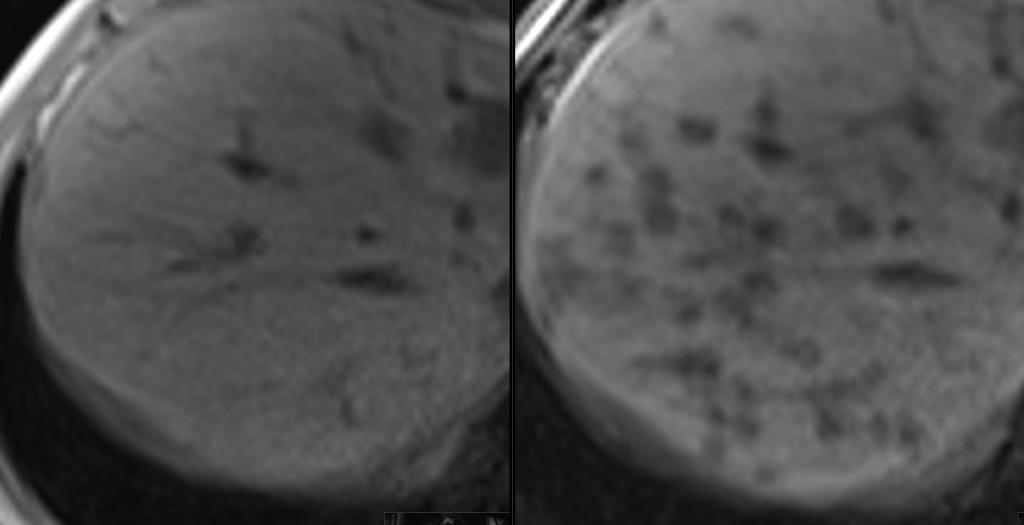

Til venstre ses leveren på et T1-vektet MR-bilde i inn-av-fase-sekvens hos en kvinne i slutten av 70-årene med seropositiv revmatoid artritt, polymyositt og polynevropati. Hun var henvist av fastlegen på grunn av magesmerter og vekttap fra 60 kg til 46 kg de siste tre årene. Bildet til høyre viser ut-av-fase-sekvensen med multiple lavintense leverlesjoner forenelig med tilstedeværelse av fett (1). I regi av fastlegen var det tidligere tatt en CT abdomen med intravenøs kontrastvæske, som viste multiple velavgrensede, lavattenuerende lesjoner uten ekspansive trekk i høyre leverlapp, som ga mistanke om levermetastaser.

Fettholdige leverlesjoner kan representere steatose, hepatocellulære adenomer, hepatocellulære karsinomer og i sjeldne tilfeller metastaser. Lesjonene var lett hyperintense på T2-vektet sekvens, viste ingen diffusjonsrestriksjon og var lavintense på T1-sekvensene etter kontrastmiddel. Disse signalkarakteristikaene gjorde at multifokal nodulær leversteatose var den mest sannsynlige diagnosen. Leverbiopsi viste kronisk portal og lett periportal betennelse med eosinofili samt steatose og steatohepatitt. Funnene kunne være forenlig med medikamentindusert leverskade. Pasienten hadde brukt metotreksat i mange år, som kan forårsake leversteatose og -fibrose. I samråd med revmatolog ble metotreksat seponert.

Multifokal nodulær steatose er en sjelden presentasjon av leversteatose som ofte vekker mistanke om primær eller sekundær malign leversykdom. MR av lever er anbefalt for karakterisering og vil typisk vise signalbortfall i lesjonene på ut-av-fase T1-vektet MR. Ultralyd med kontrast kan også gi diagnosen i noen tilfeller (2). Når diagnosen kan stilles med høy grad av sikkerhet ved bildediagnostikk, kan biopsi unngås. Lesjonene kan da følges opp radiologisk (3).